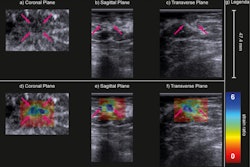

(A) Examples of B-mode images for the measurement of membrane thickness of implants from each of the four types of implants. Images are presented at the same scale. Membrane thicknesses (B) and then shear moduli measured by ARFI method (C) are compared without dissociation as a function of prosthesis age or implantation time. (NS: p-value > 0.05, *: p-value < 0.05, **: p-value < 0.01, ***: p-value < 0.001). Images are available for republishing under a Creative Commons license (CC BY-NC-ND 4.0 Deed) and courtesy of the Journal of Biomechanics.